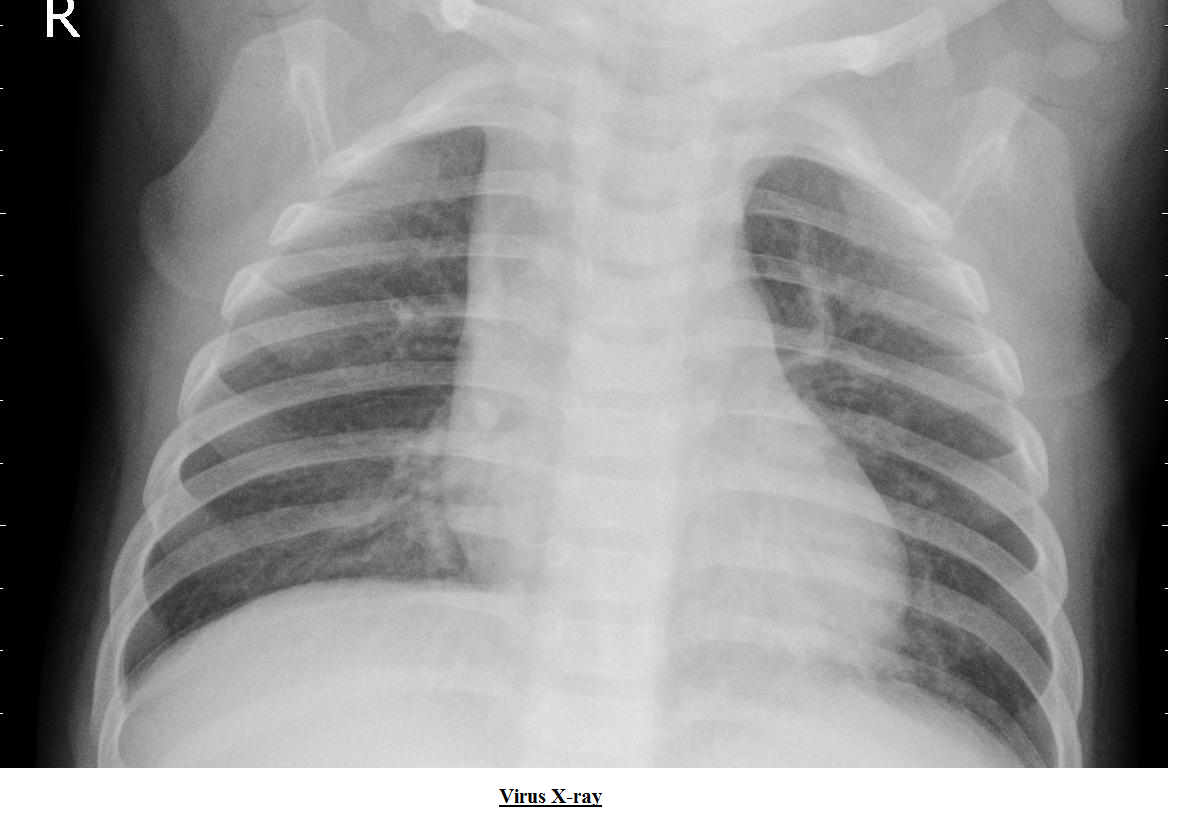

4. Pneumonia detection using x-rays

The input is various X-ray images. The X-ray images are classified into abnormal and normal. Due to less number of images, the image augmentation is done to boost the performance of CNN.